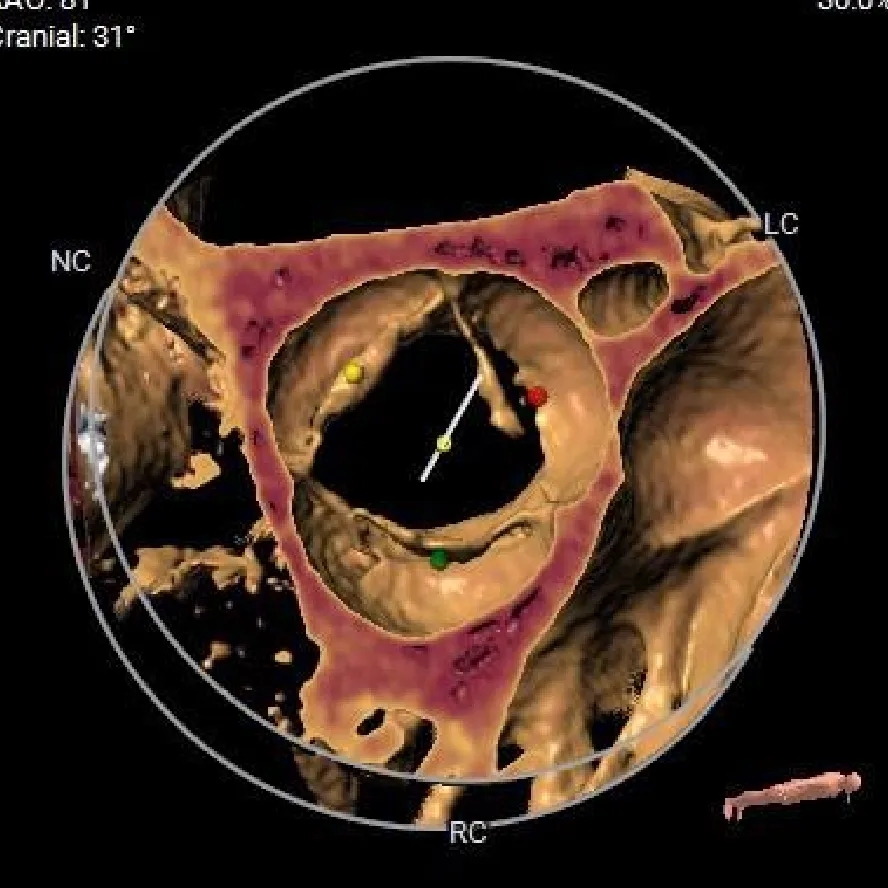

VR图

SOV:

35.2*32.7*31.9mm

STJ:

33.3mm

AAO:

44.6mm

冠脉风险评估

LCA Height

RCA Height

LCA & Leaflet

RCA & Leaflet

左室测量

工作体位

右窦中心

左右重合

左冠切线